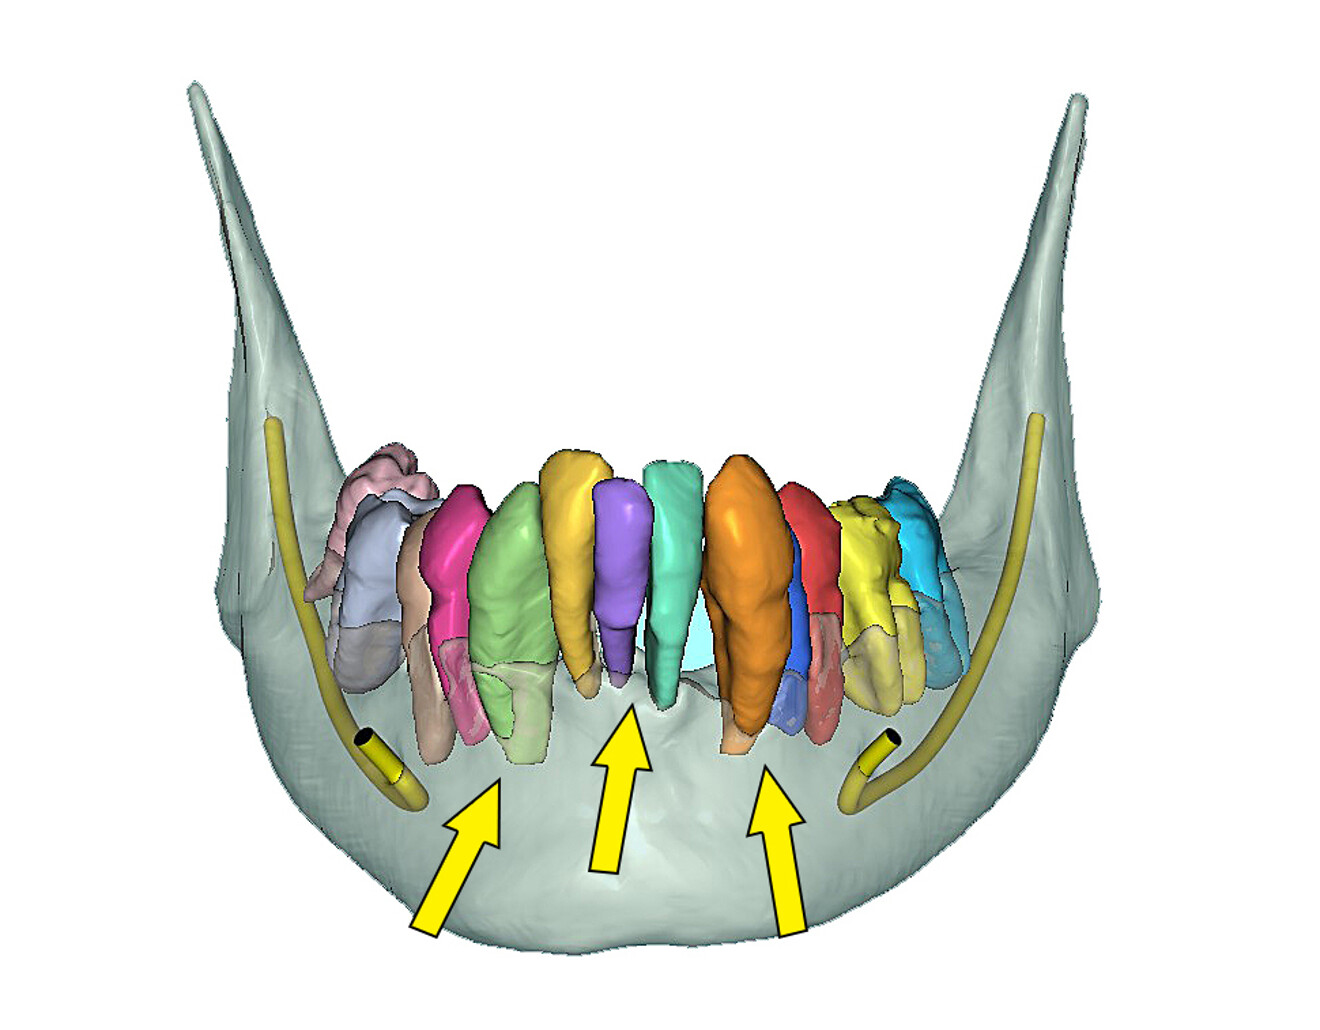

The mandibular arch followed a similar surgical protocol utilising a bone-borne surgical guide after tooth extraction and bone reduction. The advanced bone and tooth segmentation illustrated the severe bone loss almost to the apex of many of the mandibular roots (Fig. 13a). Using selective transparency, the roots and bone could be closely evaluated (Fig. 13b). 3D volumetric reconstruction simulating the post-extraction bone helped provide a unique view of the mandibular bony anatomy (Fig. 14a) and aided in finalising the location of each implant (Fig. 14b).

Fig. 13a: Fully segmented mandibular bone and teeth.

Fig. 13b: Selective transparency view visualising the roots, bilateral mental nerves and inferior alveolar nerve (yellow arrows point to the apices of the roots, showing the extent of the bone loss).